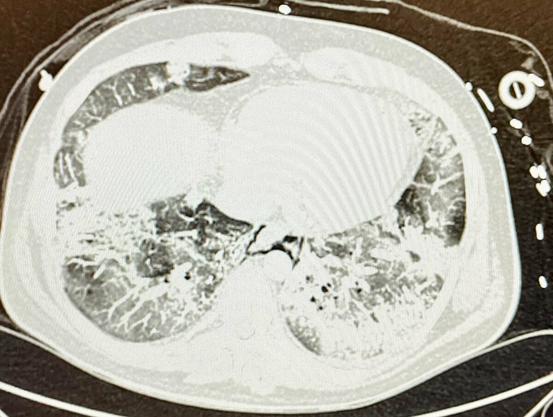

Intensiv-Visite heute: Patient mit #COVID19, 38 J., ohne Vorerkrankungen, ohne Impfschutz.

Schwere Lungenschädigung, zentrale Lungenarter…